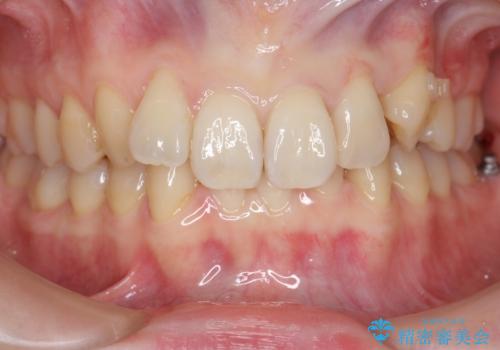

前歯のがたつき、八重歯 インビザラインで抜歯矯正

- 前歯のがたつきを主訴に来院。

下の前歯は生まれつき1本少ない状態でした。

左上の犬歯が入りきらずねじれており、かみ合わせもずれていました。

左上の小臼歯を1本抜いて治療しています。

前歯は内側に傾いており(ラビッティング)、過蓋咬合(深いかみ合わせ)を呈していました。

難しい治療でしたが綺麗に咬み合わせることができ、また前歯もしっかり当たるように治療できました。